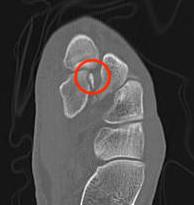

CT

Dorsal subluxation of the metatarsal